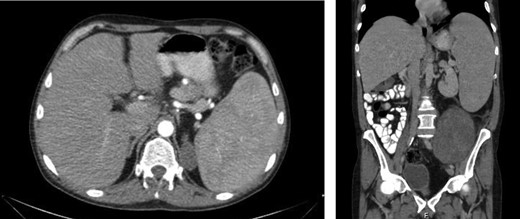

Laboratory work-up revealed a white blood cell count (WBC) of 1.0 K/ul, an absolute neutrophil count of 680, and an absolute lymphocyte count of 310. He was anemic with a hemoglobin of 6.9 g/dl. Rheumatoid factor was elevated to 180 IU/ml. An antinuclear antibody screen was positive at 1:320. Computed tomography (CT) of the abdomen and pelvis showed an enlarged spleen and a large heterogeneous mass in the left abdomen extending into the pelvis (Figs 1 and 2). A bone marrow biopsy showed abnormal CD3+ and CD8+ T-cell lymphocytosis with TCR(beta)+ and CD57+, consistent with the diagnosis of T-cell large granular lymphocytic leukemia.

An enlarged spleen (16 × 10 × 22 cm) was identified on CT imaging obtained as part of the work-up of a palpable left abdominal mass.